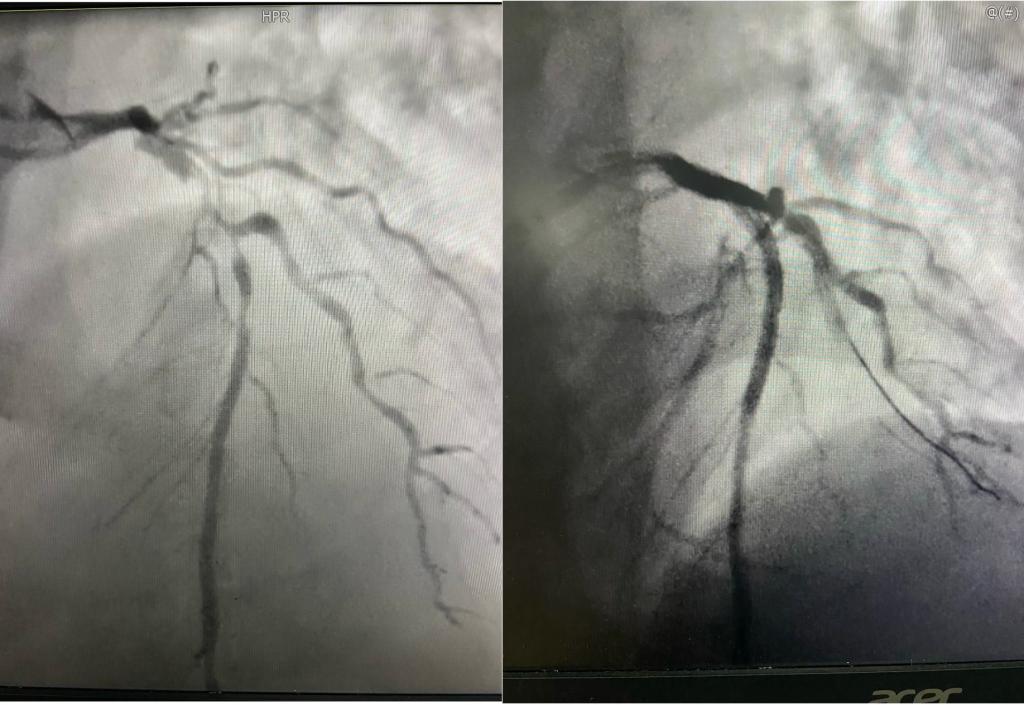

48岁的朱先生1月前因突发胸痛于当地医院诊断为急性前壁心肌梗死,后出现心源性休克,当地药物治疗后血压难以维持转入我院。入院时外院心脏彩超提示全心增大、室壁运动弥漫性减弱、EF仅0.2,使用升压药血压80-90/40-60mmhg,再次复查心脏彩超该患者还合并左心室血栓,该患者猝死风险高、预后差。入院后予以升压、强心、抗凝、冠心病药物治疗,于11月9日行冠脉造影示前降支口部95%局限性狭窄、近中段90%节段性狭窄,回旋支主支次全闭、OM2近端90%狭窄,右冠脉开口后完全闭塞,可见左冠脉向右冠脉发出侧枝循环。由于患者心功能极差、血流动力学不稳定,暂缓PCI,术后请心外科评估该患者心功能差无法耐受开胸搭桥手术。患者及家属商议后要求行PCI术。患者冠脉病变复杂、心功能极差,PCI术中导丝或球囊等一旦占据掉血管中仅存一丝的血流,就随时会出现循环崩溃、室速室颤等恶果,可假如不去开通病变血管,患者极有可能因为任何一个不稳定因素而导致血管急性闭塞、血流全无,做与不做都可谓命悬一线。

前降支术前、术后